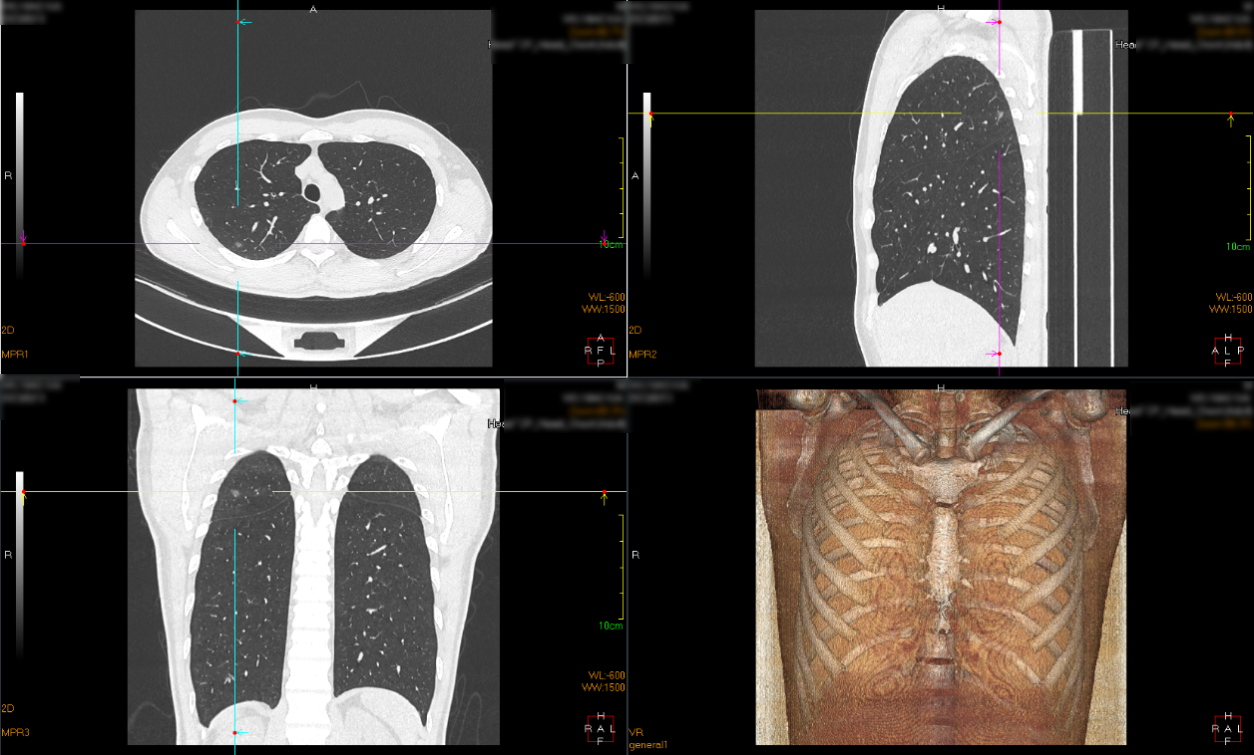

手术当天中午,患者进入手术室,进行常规气管插管全身麻醉。在进入麻醉状态后,患者取右侧卧位,在右上肺病灶的后背投影处粘贴CT快速引导垫。

激光导航定位

再次扫描,评估定位情况;摆放体位,消毒,开始手术;右上肺后段切除后,切开病灶,可见病灶与定位点毗邻,术中快速病理示右上肺结节为微浸润腺癌,手术顺利,患者安然返回病房。

我院使用的移动式C臂是在全球推出的新一代可移动式C臂CT系统,集C臂和CT功能于一身,可以即时且方便的快速移动到所需手术的房间内。具有占地小、移动灵活、扫描时间短、效率高、精准度高的特点。同时术中CT图像成像质量高,适合4毫米以上肺小结节及肺实质等软组织CT成像;而且辐射剂量低,仅为传统CT的1/8。目前该系统已被美国MD Anderson癌症中心,约翰霍普金斯大学医院,克利夫兰诊所等世界顶级医疗机构引入,用于“一站式”肺小结节的介入诊疗。使用移动式C臂CT术中对肺小结节患者进行术中CT扫描,显示结节,引导置入定位针,不出手术室,即可完成"一站式"肺结节定位及精准切除。避免患者在CT室和手术室间来回奔波,消除了清醒状态下的穿刺痛苦,也大大降低了出血、气胸等并发症的发生机率。

另外使用的激光导航定位系统,辅助医生进行肺结节定位、穿刺等操作流程,使得肺结节经皮穿刺更简单、更安全、更快捷。